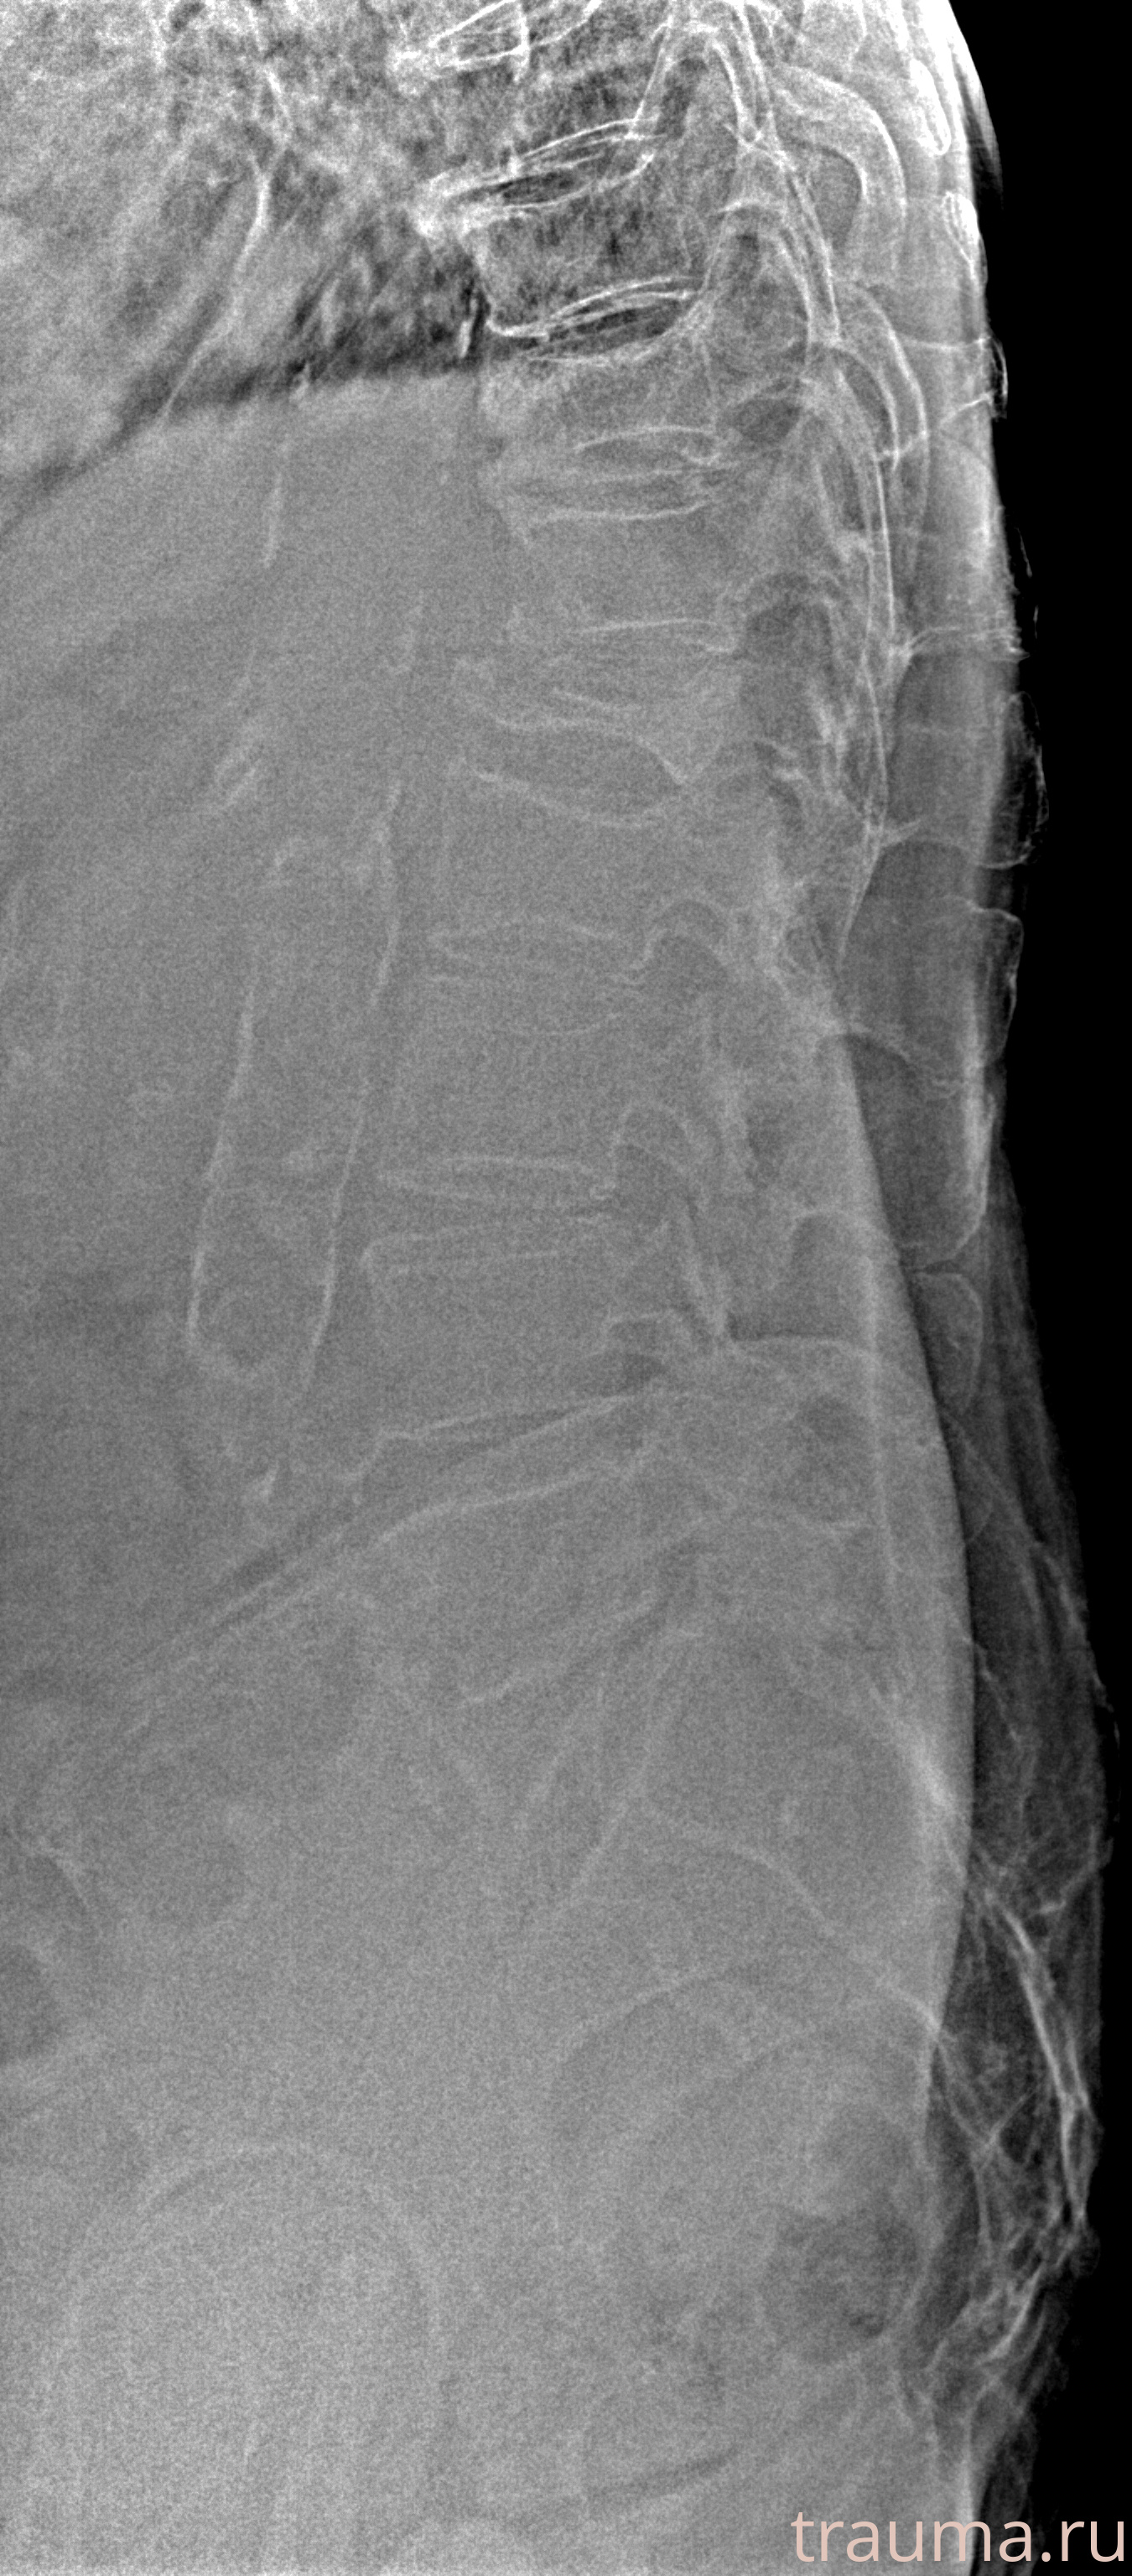

Рентген на дому: по вашему адресу приезжает врач-рентгенолог, травматолог-ортопед с мобильным рентгеновским аппаратом, проводит диагностику травмы или заболевания, делает необходимые рентгенограммы, дает рекомендации по дальнейшему лечению. Получить качественные снимки в домашних условиях возможно благодаря уникальной методике, разработанной МосРентген Центром для института  Склифосовского